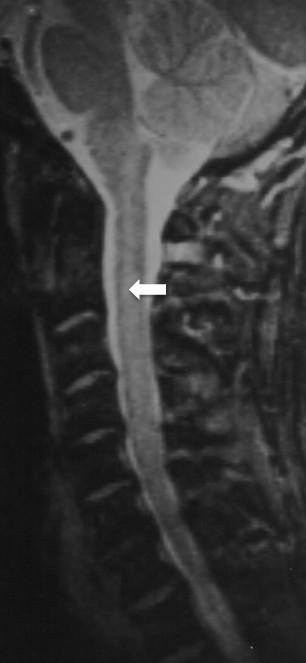

Intracranial dural arteriovenous fistulas are abnormal communications between higher-pressure arterial circulation and lower-pressure venous circulation. This abnormal communication can result in important and frequently misdiagnosed neurological abnormalities.A case of rapid onset paraplegia following cervical chiropractic manipulation is reviewed. The patient's generalized spinal cord edema, lower extremity paraplegia and upper extremity weakness, were initially believed to be a complication of the cervical spinal manipulation that had occurred earlier on the day of admission. Subsequent diagnostic testing determined the patient suffered from impaired circulation of the cervical spinal cord produced by a Type V intracranial arteriovenous fistula and resultant venous hypertension in the pontomesencephalic and anterior spinal veins.The clinical and imaging findings of an intracranial dural arteriovenous fistula with pontomesencephalic venous congestion and paraplegia are reviewed.This case report emphasizes the importance of thorough and serial diagnostic imaging in the presence of sudden onset paraplegia and the potential for error when concluding atypical neurological presentations are the result of therapeutic misadventure.

颅内硬脑膜动静脉瘘是高压动脉循环与低压静脉循环之间的异常连通。这种异常连通可导致重要且常被误诊的神经学异常。本文回顾了一例颈椎整脊手法治疗后迅速出现截瘫的病例。患者出现全身性脊髓水肿、下肢截瘫和上肢无力,最初被认为是入院当天早些时候进行颈椎手法治疗的并发症。随后的诊断测试确定患者患有由V型颅内动静脉瘘导致的颈段脊髓循环障碍以及脑桥中脑和脊髓前静脉的静脉高压。本文回顾了伴有脑桥中脑静脉淤血和截瘫的颅内硬脑膜动静脉瘘的临床和影像学表现。本病例报告强调了在突然发生截瘫时进行全面和系列诊断性影像学检查的重要性,以及在认定非典型神经学表现是治疗失误所致时可能出现的错误。